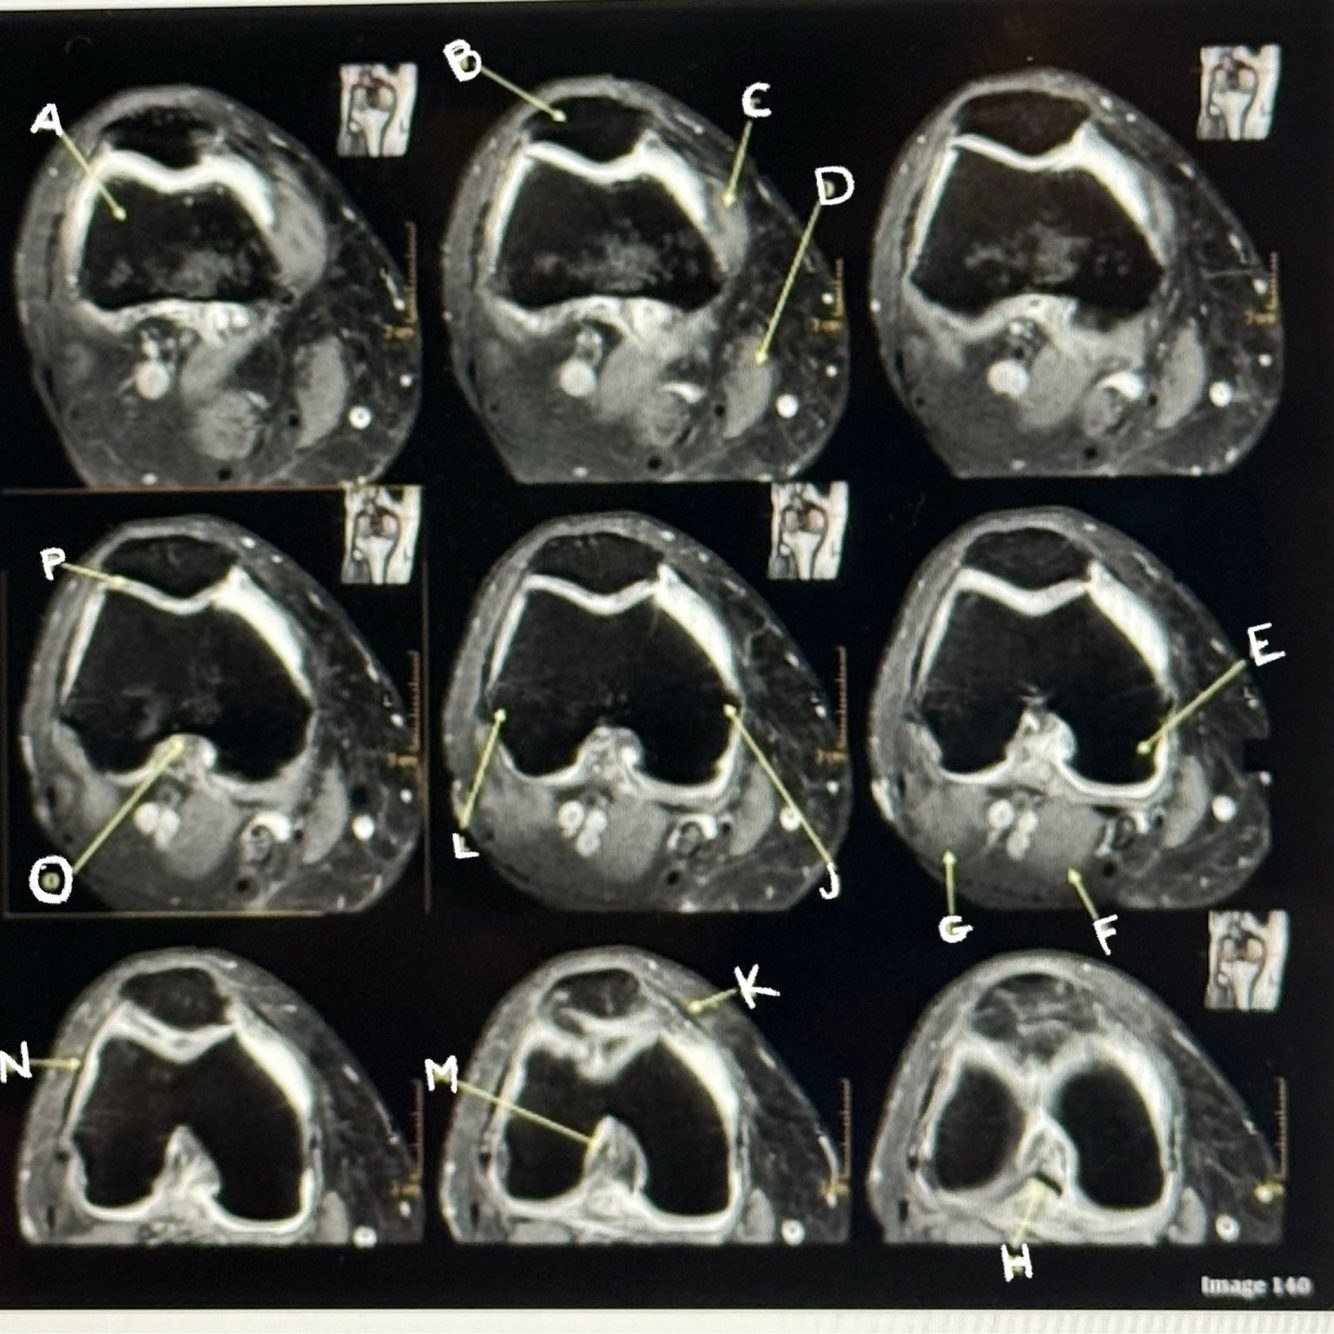

Letter C points to the

Vastus medialis muscle

Letter D points to the

Sartorius muscle

Letter E points to the

Medial condyle

Letter F points to the

Medial head gastrocnemius

Letter G points to the

Lateral head gastrocnemius

Letter H points to the

Posterior cruciate ligament

Letter J points to the

Medial epicondyle

Letter K points to the

Medial retinaculum

Q

Letter B points to the

Femur

Letter A points to the

Patella

Letter P points to the

Articular cartilage

Letter M points to the

Anterior cruciate ligament

Letter N points to the

Lateral retinaculum

Letter O points to the

Intercondylar fossa

Letter L points to the

Lateral epicondyle

Posterior cruciate ligament (PCL)